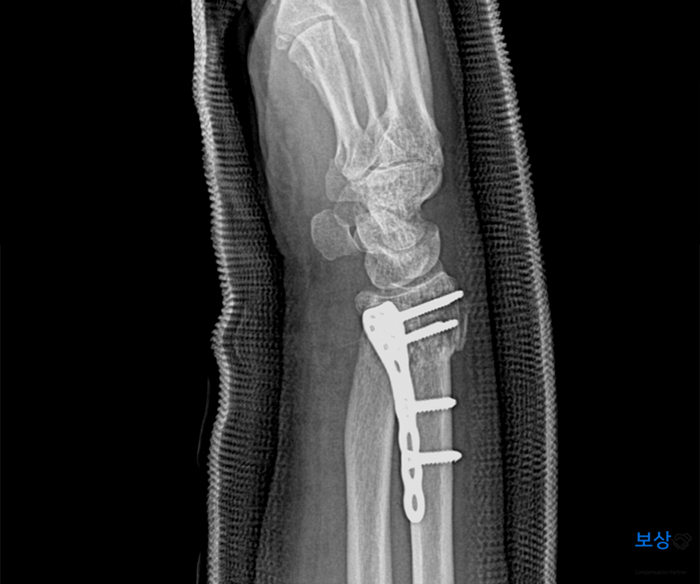

또한 골편이 여러 조각으로 나뉘는 분쇄골절의 양상을 띄었는데요. 이 역시 심한 골절상임을 알려주는 부분입니다. 즉시 수술적 치료가 필요하였으며, 관혈적 정복술 및 금속 내고정술 후에 깁스하여 안정을 취하게 되셨습니다.